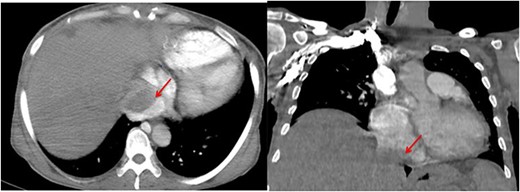

The pathological and immunohistochemical examination suggested a smooth muscle mesenchymal tumor without signs of malignancy, raising the possibility of disseminated intravascular leiomyomatosis or a BML (Figs 4 and 5). The thoracic computed tomography (CT) indicated the presence of a mass in the inferior vena cava extending into the right atrium. Magnetic resonance imaging (MRI) confirmed uterine leiomyomatosis (Fig. 3). This explains the origin of the mass in the right atrium.

Angio-CT thoracic images reveal the presence of a mass in the inferior vena cava extending into the right atrium (arrow).